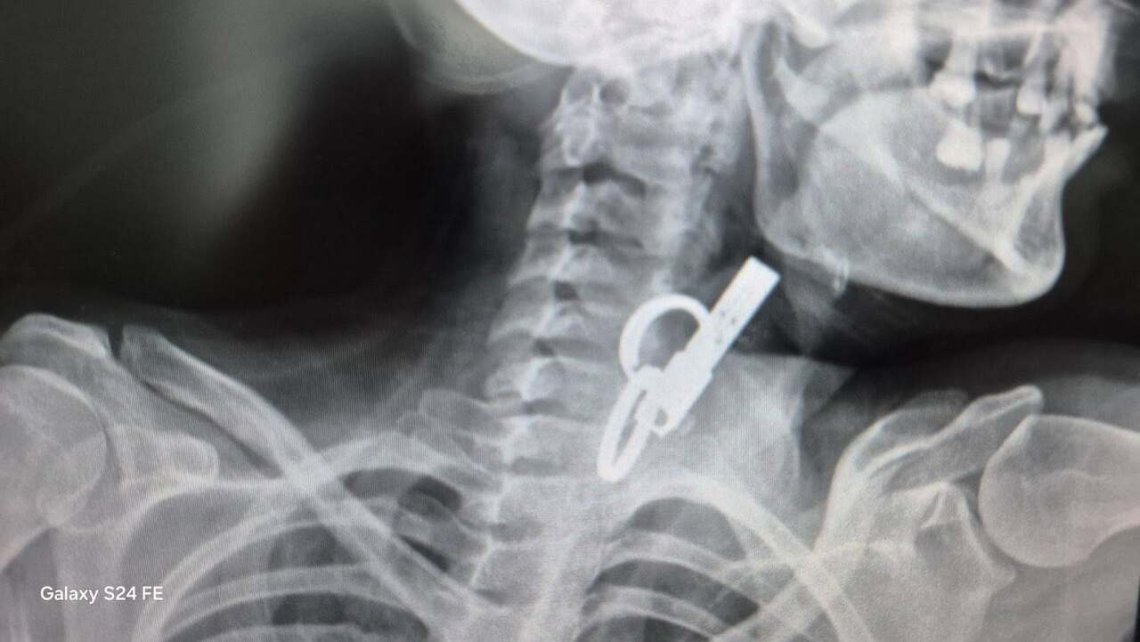

У Гусятині, що на Тернопільщині, лікарі витягнули у 40-річної пацієнтки ключ від дверей. Жінка його ковтнула, щоб не пускати родичів у хату.

- Це дуже показовий випадок, що нам вдалося її врятувати. Як свідчить практика, переважно такі хворі гинуть. Спочатку ми не могли зрозуміти, що застрягло у стравоході. Це були якісь металеві кільця, які стояли зверху, а далі було ще якесь чужорідне тіло. Я здогадався, що це може бути ключ від дверей і почав його обережно витягувати, – розповів Олександр Садовий.

З’ясувалося, що ключ жінка проковтнула, щоб не віддати його родичам і, щоб вони не мали доступу до її помешкання. Лікар додає, що в обласну лікарню у Тернопіль не ризикнули везти пацієнтку, оскільки її вже доставили в стані шоку, жінку просто б не довезли. Рішення про операцію приймали за лічені хвилини.